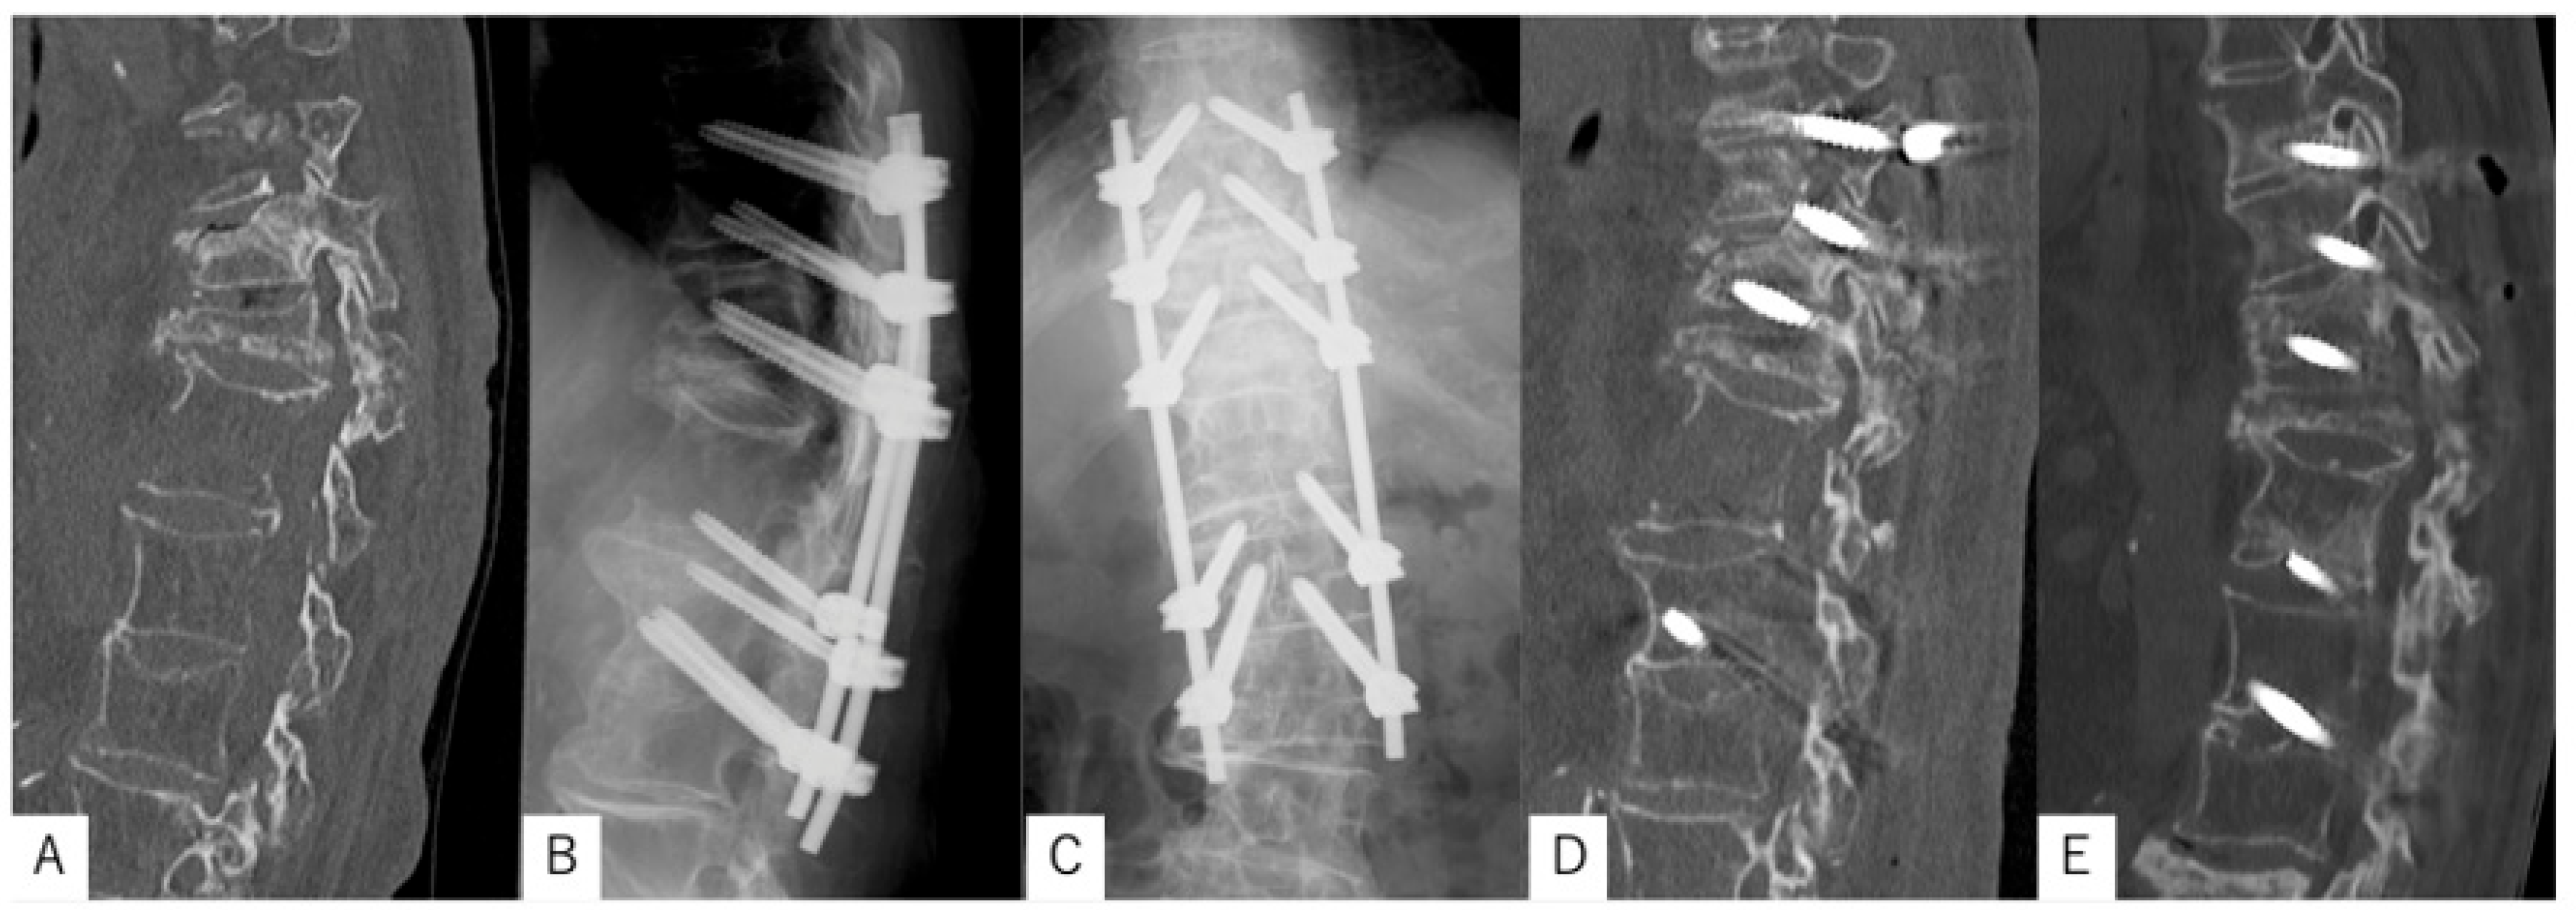

3.2. Case Presentation 2